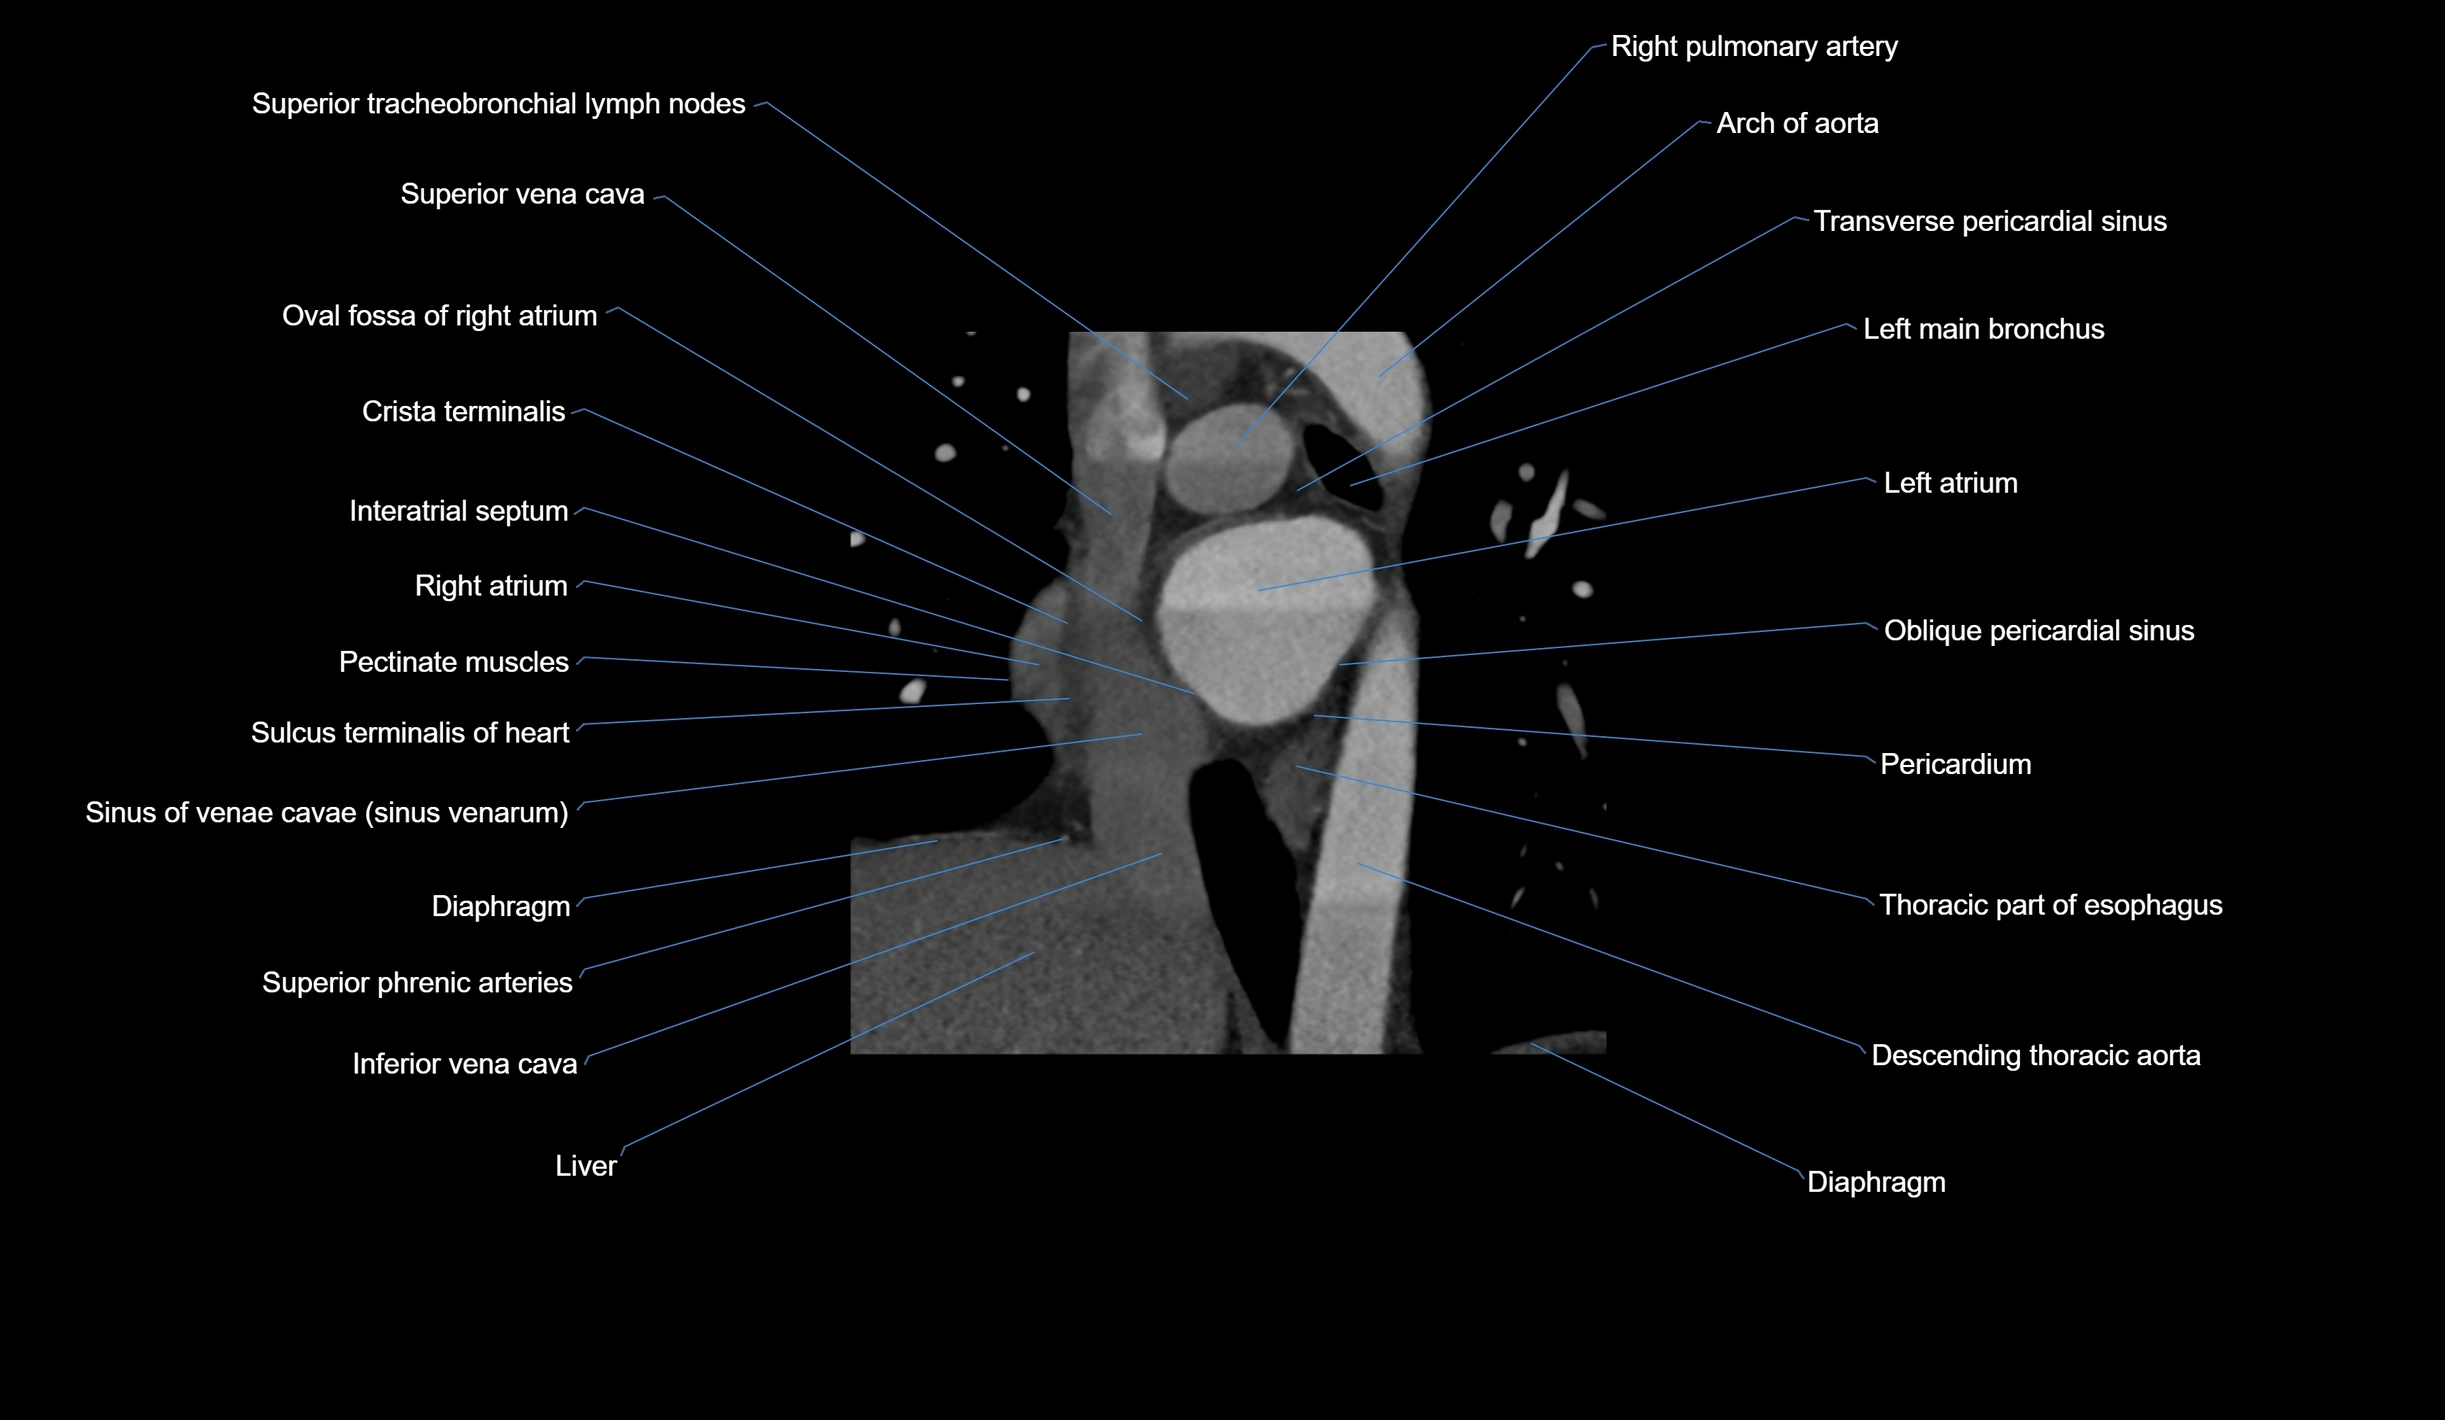

- Arch of aorta

- Azygos vein

- Crista terminalis

- Interatrial septum

- Left atrium

- Left main bronchus

- Oblique pericardial sinus

- Oval fossa of right atrium

- Pectinate muscles

- Pericardium

- Right atrium

- Right pulmonary artery

- Sinus of venae cavae (sinus venarum)

- Sulcus terminalis of heart

- Superior tracheobronchial lymph nodes

- Superior vena cava

- Transverse pericardial sinus